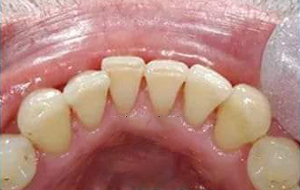

• Oral prophylaxis – A simple procedure of professional cleaning of teeth dislodges the plaque deposits on the teeth and hence maintains the health of the gums. This procedure should be done at an interval of 6 months.